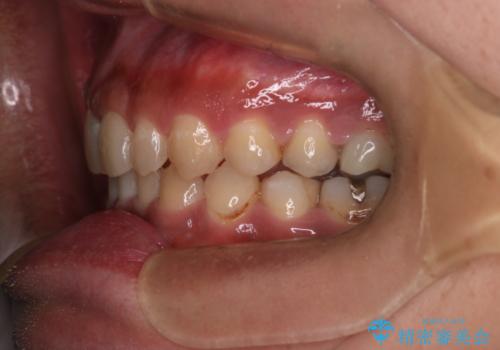

【モニター】インビザライン 前歯の捻れを治したい

- 30代男性

- 矯正装置

- インビザライン

- 上下の前歯のがたつきを主訴に来院されました。インビザラインで治療可能と判断致しましたので、IPR(歯と歯の間を削る処置)と歯列弓拡大をして

がたつきをとる治療計画を立てました。

マウスピースをしっかり使用していただいたことで、主訴である前歯のがたつきも改善され

リファイメントも1回のみで治療を終了することが出来ました。